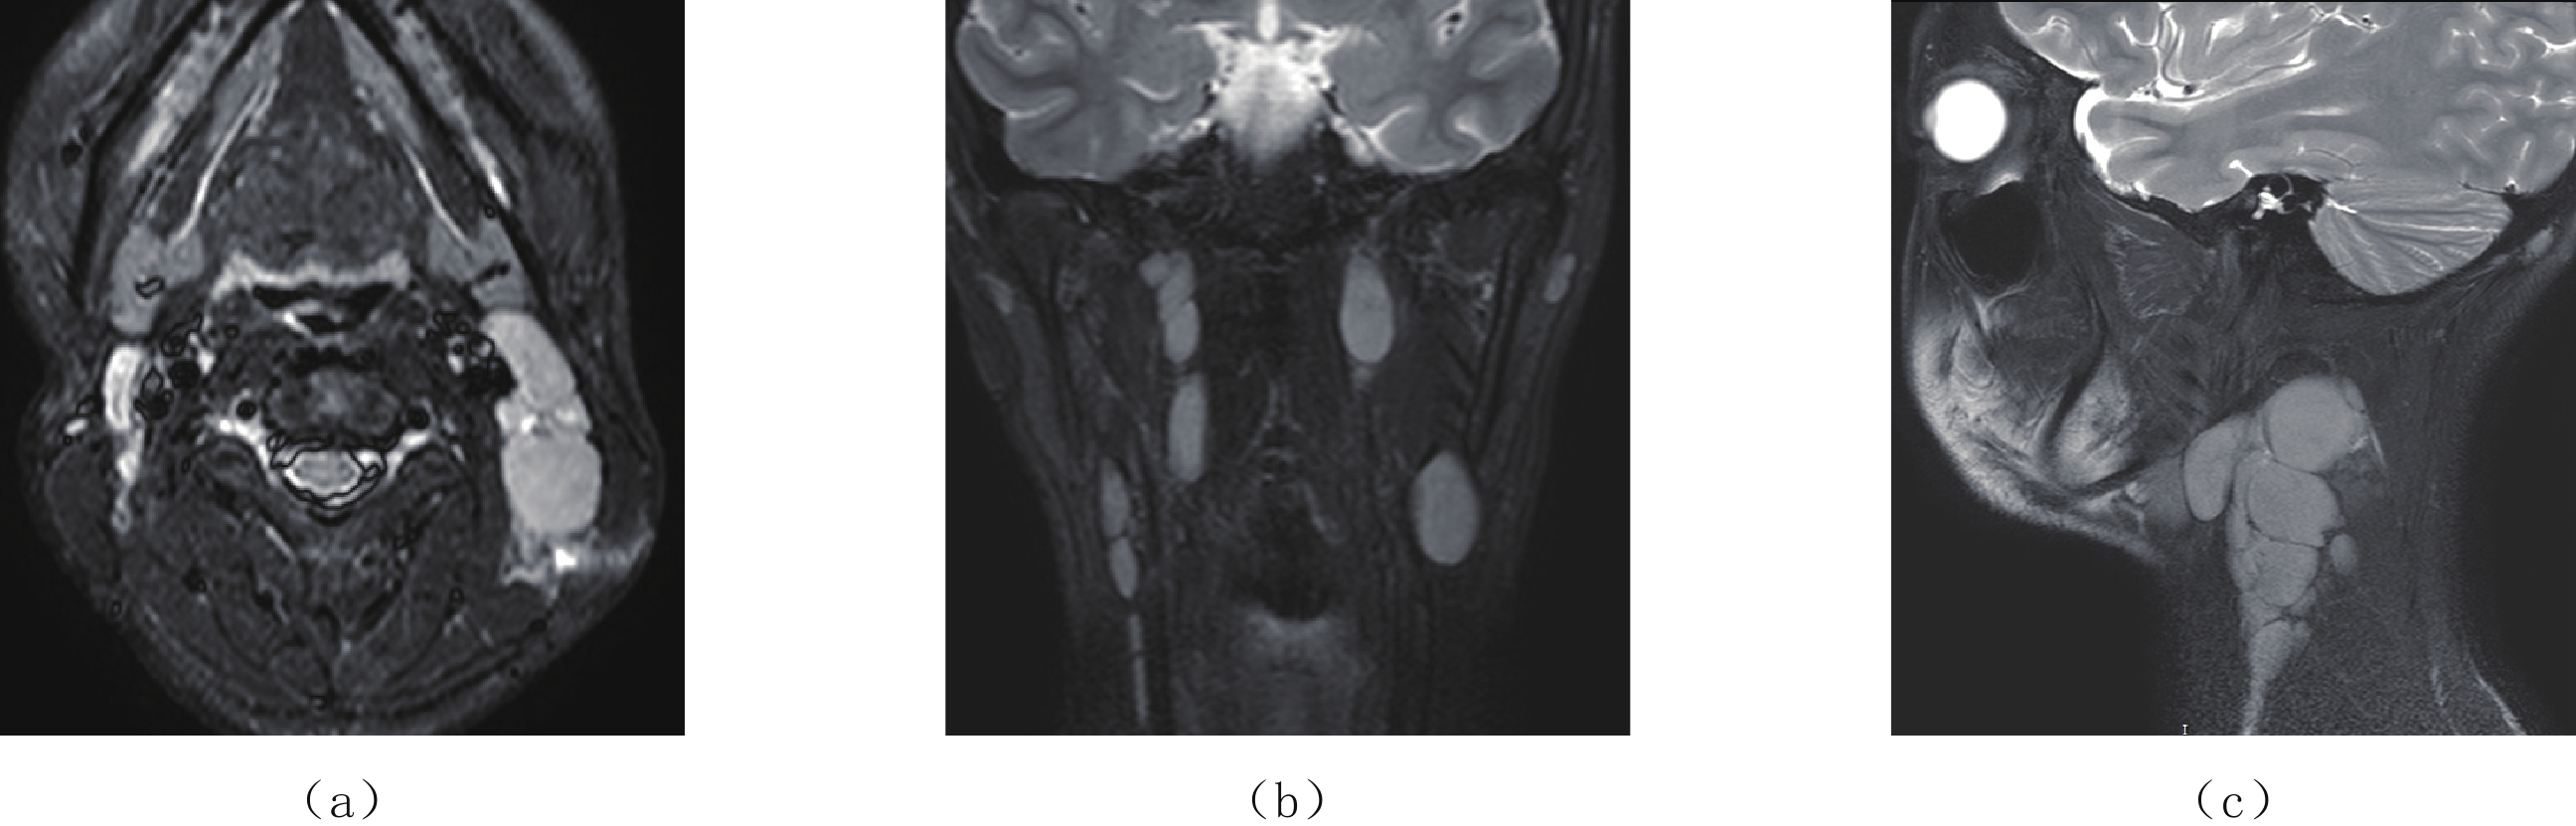

Epstein-Barr virus (EBV), also known as a gamma herpesviru, has the characteristics of lymphophilic tissue. EBV is one of the most common human viruses of the human cold virus group and the first human tumor virus found. Infection with EBV occurs by the oral transfer of saliva and respiratory secretions. Human B-lymphocytes and epithelial cells are EBV-susceptible host cells. First EBV infection often occurs in infancy and in childhood. EBV-associated diseases include infectious mononucleosis, EB virus associated hemophagocytic lymphoproliferative disorder (EBV-HLH), chronic active EBV Infection, EBV infection-associated autoimmune disease. EBV infection can also cause the proliferative diseases of the infected cells, such as various non-malignant lymphoproliferative diseases, lymphomatoid granulomatosis, EBV associated with many more malignant diseases including Burkitt′s lymphoma, Hodgkin′s lymphoma, Diffuse Large B-Cell Lymphoma, NK/T cell lymphoma, nasopharyngeal carcinoma, a subset of gastric carcinomas, and many more. This paper mainly focuses on EBV associated lymphoproliferative diseases and imaging characteristics in children.